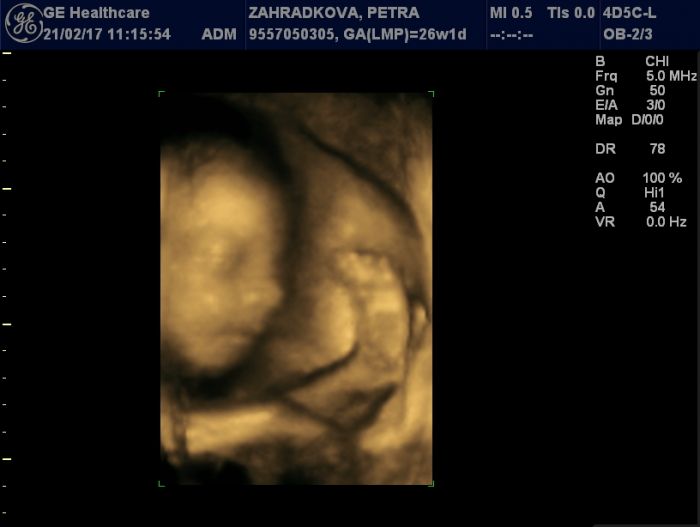

[980416] No my měli štěstí že se jí vůbec povedlo vyfotit. Pořád byla otočená na druhou stranu. Tak mě poslali na čokoládu a trochu se projít a vyšla z toho tahle hezká. :-)

Ja jdu zitra na kontrolu ve 30tt. Tak uvidime kolik vazime a merime :D ale prijdu si jak kdyz je jako na kolotoci. Neda a neda pokoj s kopanim. Uz aby mel malo mista a tolik se nemrskal :D :D :D neni se za co stydet. Holt nekdo pred porodem vypada ze jenom ztloustnul a nekdo vypada jak velryba. Ale zas je za co chytit a do ceho kopnout. A manža se ma čim prikrejt no ne? :D :D nam se tohle povedlo az na druhej termin. S prvnim byl zady a skoval oblicejik pod ruce ale i na podruhy se mlel tak tohle je jedina hezka co mame za ty penize